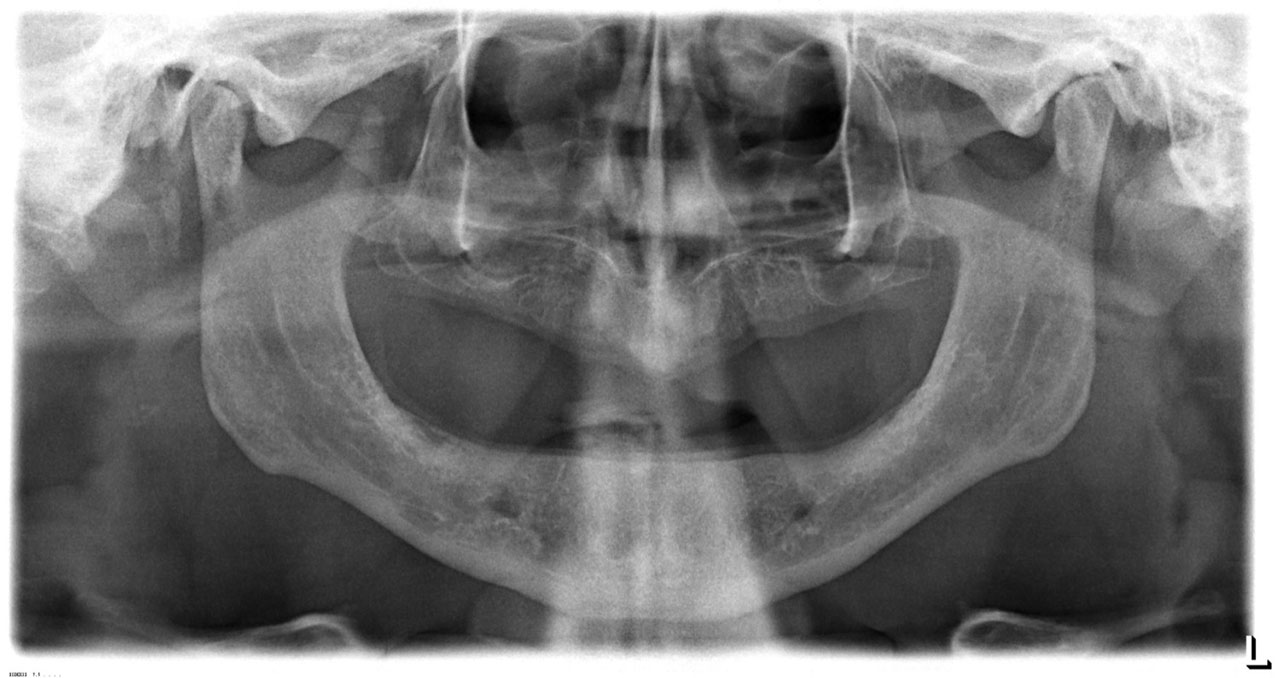

• esettanulmany-01

Implantáció előtt, gyulladt, törött fogak.

Teljes fogatlanság.

• esettanulmany-14

Alsó- felső fogatlan állcsont teljes implantációs helyreállítása.